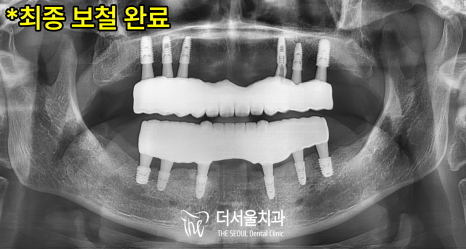

윗턱의 잇몸뼈에 염증이 있던 영역은

뼈이식을 통해 보강해드리며

정밀분석 결과값대로,

오차 없이 알맞은 자리에

위/아래 각각 6개의 픽스처를 식립했습니다.

몇 달간 단단하게 유착되길 기다린 뒤

0.1mm단위로 정밀하게 제작된

최종보철을 올려드렸습니다.